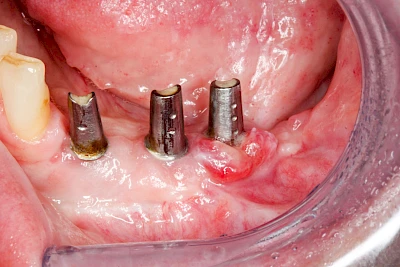

Bei Implantaten – also operativ eingebrachten künstlichen Zahnwurzeln – kann der Körper die Bakterien auch nicht so gut abwehren. Hier spricht man im Fall einer Entzündung von einer Peri-Implantitis, also einer Entzündung um das Implantat herum.